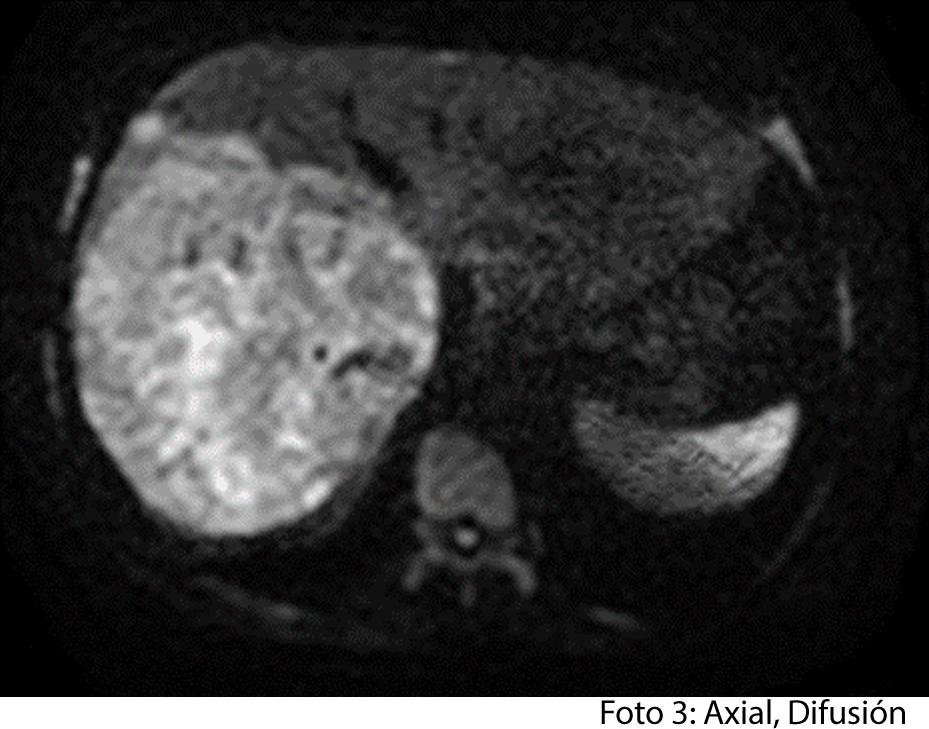

TECNICA EMPLEADA

Se procede a atender a paciente luego de cumplir con los protocolos para la realización de estudios de resonancia, paciente ingresa a zona 4, se coloca en posición decúbito supino, se utiliza gating respiratorio, estudio se obtiene con uso de bobina phase arrays, PSP Axial, sagital y coronal, secuencias Se y Gre, ponderadas a T1 y T2, se administra medio de contraste hepato especifico y se utiliza protocolo para estudio dinámico.

HALLAZGOS IMAGENOLOGICOS

• HEPATOCARCINOMA FIBROLAMINAL QUE COMPROMETE TODO EL LÓBULO DERECHO DEL HÍGADO

Es un método utilizado en el cual podemos observar una gran masa localizada en los segmentos del hígado también se puede medir el diámetro de la masa, el hepatocarcinoma también puede presentar focos hemorrágicos y además podemos captar de manera heterogénea el medio de contraste intravenoso. En los hepatocarcinomas podemos ver obstruyendo parcialmente la vena porta. Adenomegalias los cuales nos indican Los hallazgos como primera posibilidad diagnóstica, carcinoma hepatocelular fibrolamelar (CHC-FL).